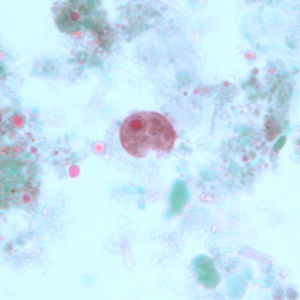

E. histolytica trophozoite

single nucleus with centrally placed karyosome. Cytoplasm contains ingested RBC’s.